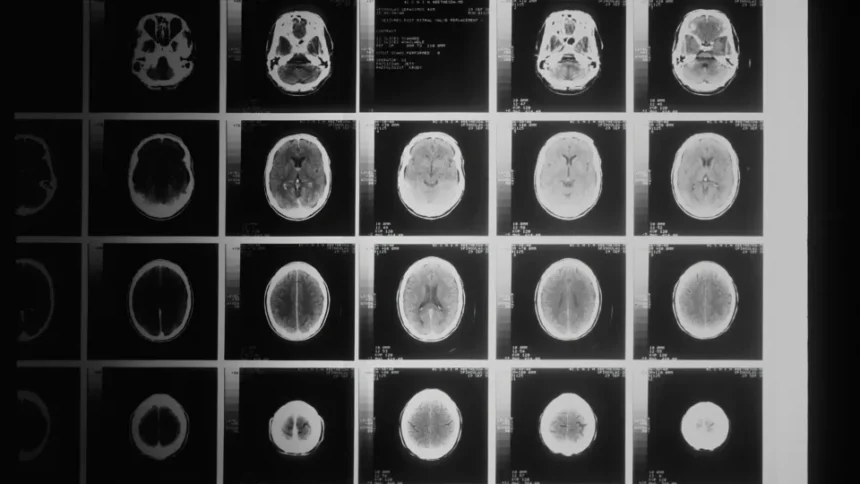

Analüüsides üle kahe ja poole tuhande magnetresonantstomograafia uuringu, märkasid teadlased selgeid erinevusi terve närvisüsteemiga inimeste ja nende vahel, kelle kognitiivsed võimed olid juba nõrgenenud. Need leiud annavad põhjust loota, et aju geomeetriast võib saada uus ja tõhus meditsiiniline tööriist.

Uuring näitas, et mitte kõik ajupiirkonnad ei vanane ühtemoodi. Mõned alad, eriti need, mis asuvad kuklapoolses ajupiirkonnas, tõmbuvad enam kokku ning see on sageli seotud tagasihoidlikumate tulemustega loogilise mõtlemise testides. See protsess võib kulgeda märksa vaiksemalt kui aju koe ilmne vähenemine, kuid selle mõju on siiski väga oluline.

Teadlased rõhutavad, et küsimus ei ole ainult ajumahus. Tähtis on see, kuidas aju pind kolmemõõtmelises ruumis muutub, sest isegi väga väikesed kujumuutused võivad mõjutada eri ajupiirkondade omavahelist koostööd. Sellised andmed näitavad, et inimese aju on keerukas ja pidevalt muutuv organ, mille struktuur peegeldab otseselt üldist vaimset seisundit.

Uuring muudab senist arusaama aju vananemisest – oluline ei ole üksnes maht, vaid ka kuju. Aju pinna geomeetria võib välja tuua väga peeneid muutusi, mis toimuvad ammu enne seda, kui ilmnevad esimesed sümptomid. See annab lootust, et tulevikus on võimalik raskeid ajuhaigusi märgata oluliselt varem.